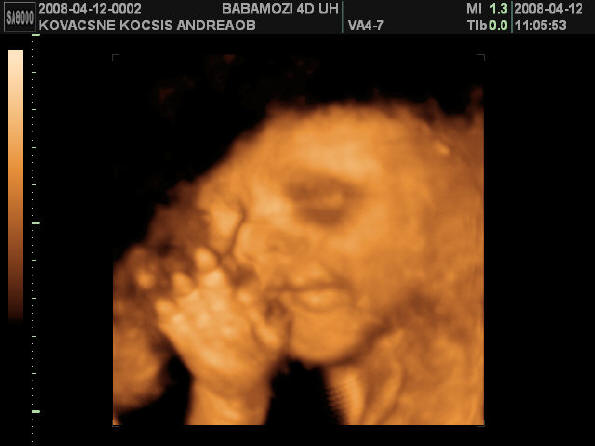

2008.04.12 10:53